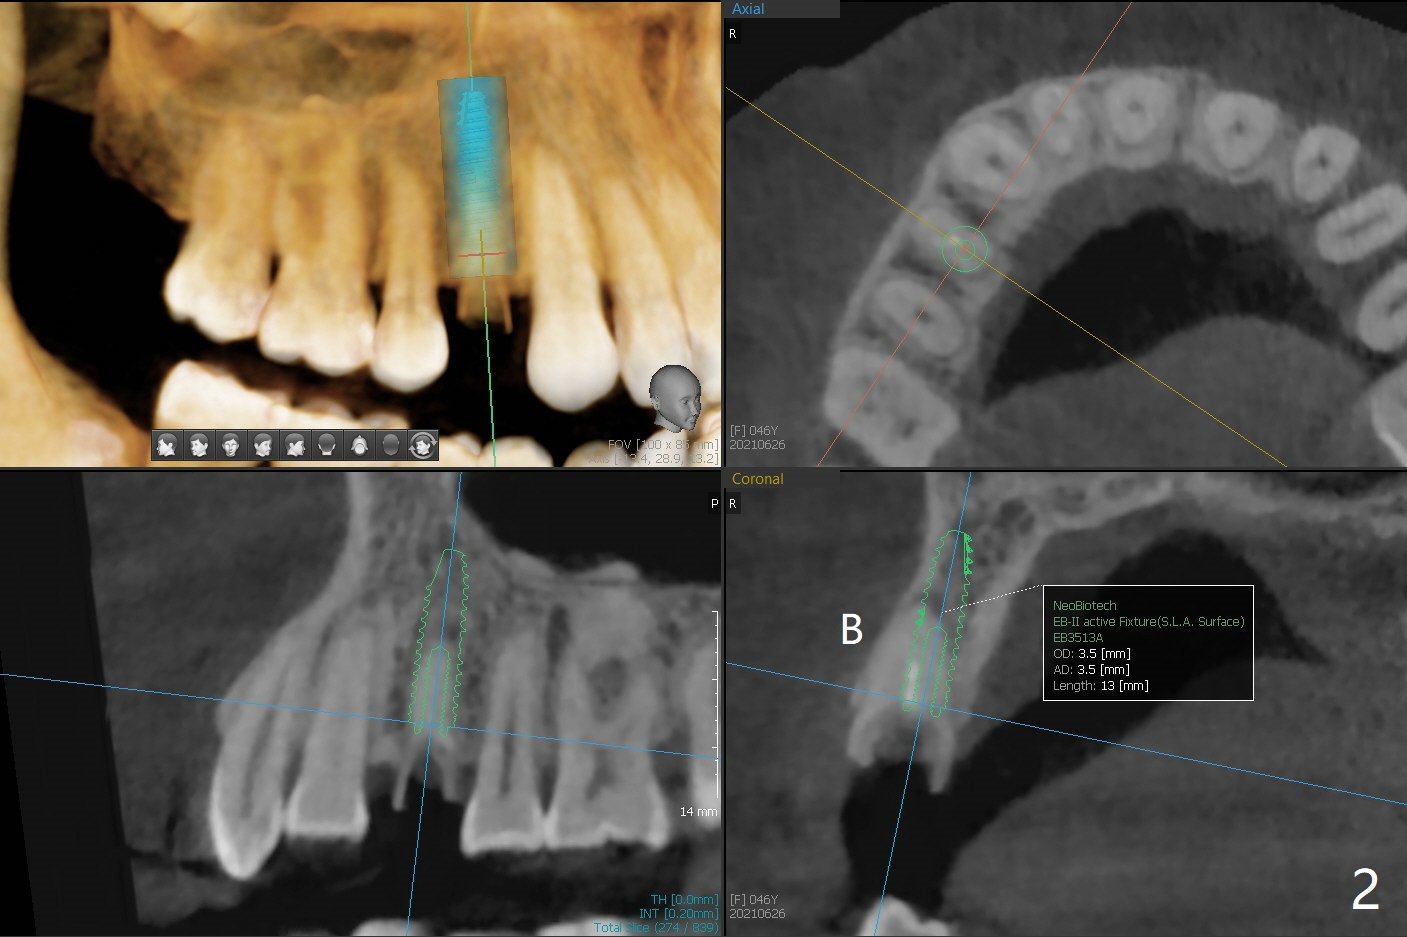

A 46-year-old woman requests implant after equigingival fracture at #5 (Fig.1). The long bone without bone loss makes it easy for immediate implant (Fig.2). PRF is not required.